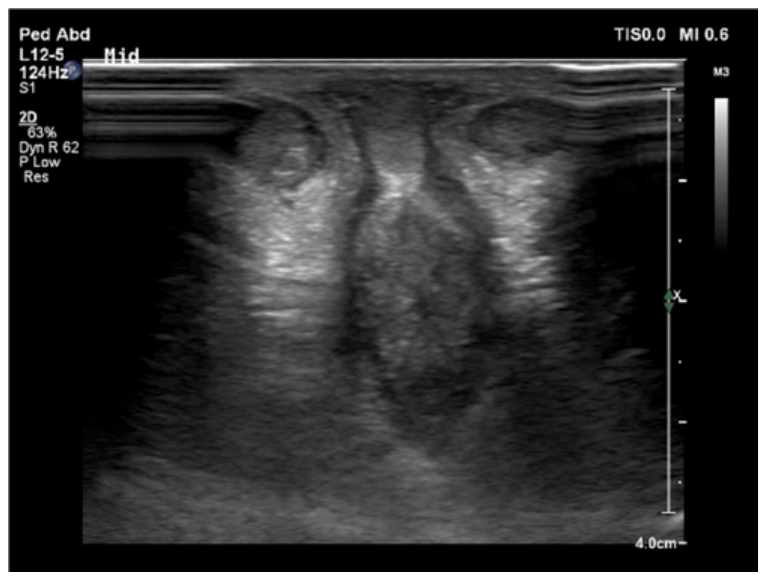

Laboratory testing showed gonadotropin and adrenal hormone levels within normal ranges for age, with normal electrolytes. Pelvic ultrasonography confirmed the presence of bilateral testes in the inguinal canals and showed no Müllerian structures or renal abnormalities. Given the combination of genital and cardiac findings, chromosomal analysis was performed.